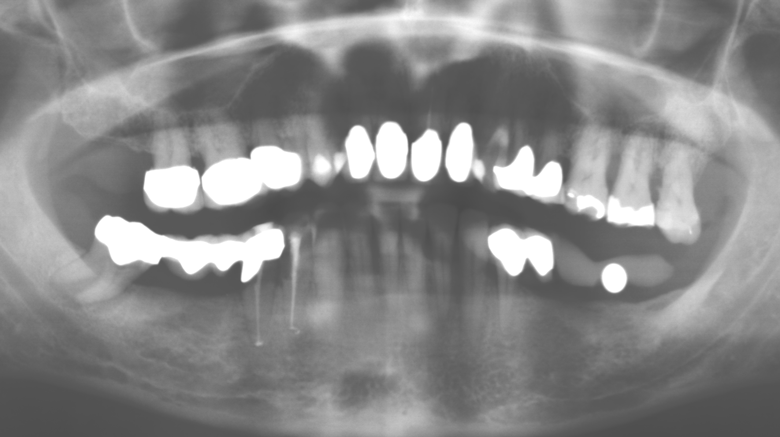

Of course, working tips for the cleaning of implant surfaces are also indispensable for SPT in patients fitted with implants. The implant cleaning attachment on the system used here is characterised by its tapered, hexagonal design. This design allows light, atraumatic penetration of the peri-implant pocket and displays a good cleaning performance (Fig. 7).

Fig. 4: Flexible probes with millimetre markings are recommended for the probing of dental implants (e.g. Colorvue Kit PCV11KIT6, Hu­Friedy). – Fig. 5a and b: A straight working tip (1P, W&H Dentalwerk Bürmoos GmbH) is a suitable instrument for use on all natural teeth. – Fig. 6: Curved working tips (3Pr/3Pl, W&H Dentalwerk Bürmoos GmbH) lend themselves to the processing of difficult-to-reach areas of the tooth and root surfaces (e.g. furcations). – Fig. 7: The tapered, hexagonal implant cleaning tip (1I, W&H Dentalwerk Bürmoos GmbH) permits atraumatic and efficient cleaning of the crown and abutment surfaces. – Fig. 8: Titanium and carbon curettes are suitable instruments for the manual cleaning of the implant surfaces.